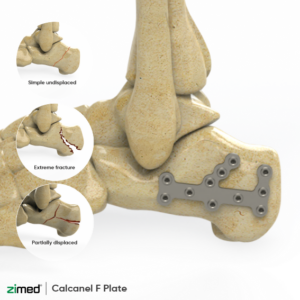

Locking Calcaneal F Plates